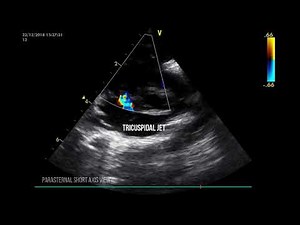

Hernia - Echo Parasternal

Long Axis View - Neonate First Breath